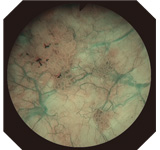

Narrow Band Imaging (NBI) is the World's Only Patented Endoscopic Light Technology for enhancing the visualization of vascular structures without the use of dyes, drugs, or contrast agents. NBI, which is strongly absorbed by hemoglobin and penetrates only the surface of tissues, is ideal for highlighting areas of increased vascularity. As a result, under NBI, capillaries on the mucosal surface are displayed in brown on the monitor, and veins in the submucosa are displayed in cyan. NBI is simple to use. With no dyes or drugs, no time limit of effectiveness, and no added cost, NBI is an easy addition to your standard procedure work flow.

NBI image